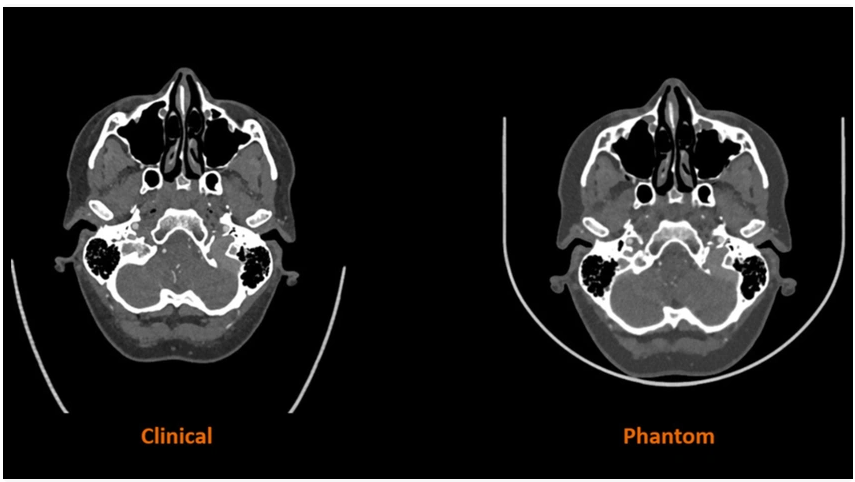

The research project will combine Stratasys’ PolyJet technology with its RadioMatrix technology, and Siemens advanced algorithm to translate scanned patient images “into specific material characteristics with radiopacity of human anatomy,” according to the press release announcing the partnership. “The solution will allow for tailored phantom manufacturing and the creation of ultra-realistic human anatomy characteristics with complete radiographic accuracy of patient-specific pathology not previously possible.”

Starting with the manufacturing of 3D-printed phantoms for smaller-scale anatomies, like of the head and neck region, the research will then progressively produce larger and more complex structures. This will lead to study’s phase one endpoint of 3D-printing a heart model and a model of an entire human torso with complete radiographic accuracy.